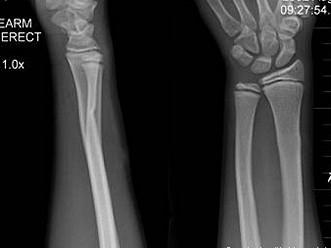

男,10岁,有外伤,根据所提供图像,选择最佳选项 ( )A、腕关节脱位B、踝关节脱位C、骺移骨折D、青枝骨折E、未见异常

选项 A、腕关节脱位 B、踝关节脱位 C、骺移骨折 D、青枝骨折 E、未见异常

答案 D